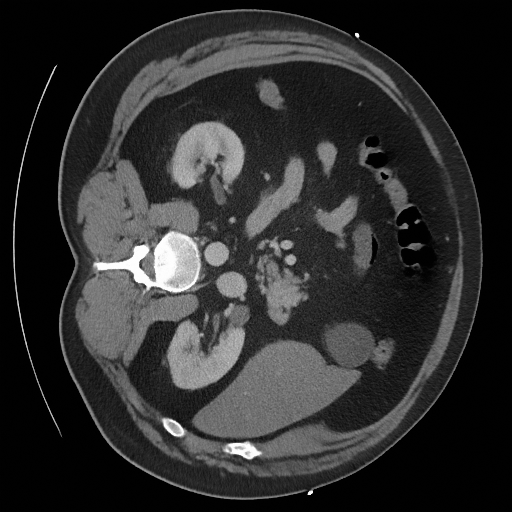

Sampling results

Original

Perturbed

Samples

Sampled